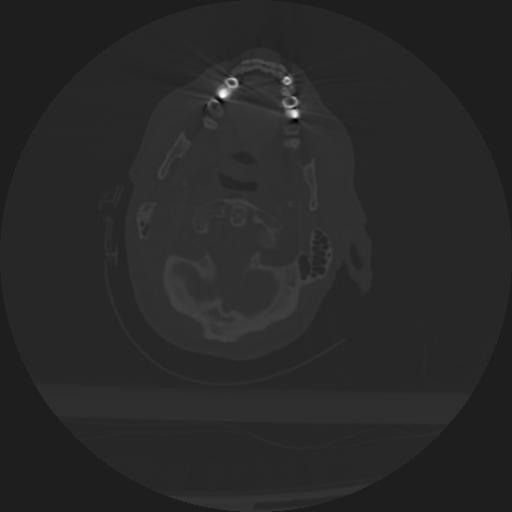

22 ANGIO,CE,Vol,0.5,ANGIO,,